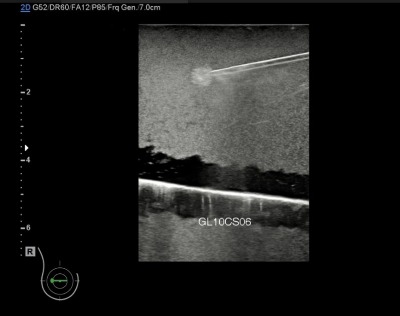

| ที่มา ข้อมูลเบื้องต้น ความสำคัญของปัญหา มะเร็งเต้านมเป็นมะเร็งที่พบบ่อยที่สุดในผู้หญิงไทยและมีแนวโน้มเพิ่มขึ้นต่อเนื่อง การตรวจคัดกรองจึงจำเป็น เพราะหากพบเร็วจะรักษาได้ทันและมีโอกาสหายสูง การใช้แมมโมแกรมร่วมกับอัลตราซาวด์ช่วยเพิ่มโอกาสพบรอยโรค ซึ่งต้องยืนยันด้วยการตรวจชิ้นเนื้อโดยใช้เครื่องมือทางรังสีช่วยนำเข็ม เนื่องจากรอยโรคมักคลำไม่พบ การฝึกใช้เครื่องมืออย่างมีประสิทธิภาพช่วยเพิ่มทักษะให้บุคลากรทางการแพทย์ จึงมีการพัฒนาเต้านมจำลองสำหรับฝึกนำเข็มอัลตราซาวด์เก็บชิ้นเนื้อ ซึ่งควรมีลักษณะเหมือนเต้านมจริง เห็นก้อนและเข็มชัด ใช้ซ้ำได้ ไม่ทิ้งรอยเข็ม และมีราคาที่เหมาะสม เทคโนโลยีทางด้านวัสดุเลียนแบบเนื้อเยื่อที่สามารถซ่อมแซมตัวเองได้ที่พัฒนามาใช้ในการทำเต้านมจำลองนี้ ได้ถูกพัฒนาต่อยอดร่วมกับเทคนิคการขึ้นรูป จึงสามารถพัฒนาอวัยวะอื่น ๆ เพื่อฝึกทำหัตถการ เช่น ผิวหนังเทียมในการฝึกเย็บ หรือตับที่สามารถแสดงภาพอัลตราซาวด์โดยที่มีรายละเอียดของเส้นเลือดหรือท่อน้ำดีเพื่อใช้ฝึกวินิจฉัย เป็นต้น |

| สรุปเทคโนโลยี • ให้ภาพอัลตราซาวด์ที่เห็นก้อนเนื้อชนิดต่าง ๆ ชัดเจน • ให้ภาพอัลตราซาวด์ของเข็มเจาะชัดเจน • สามารถใช้ซ้ำเนื่องจากวัสดุมีคุณสมบัติซ่อมแซมตัวเองได้ • สามารถต่อยอดไปสู่การพัฒนาอวัยวะอื่น ๆ เพื่อให้แพทย์ได้ฝึกทำหัตถการ |